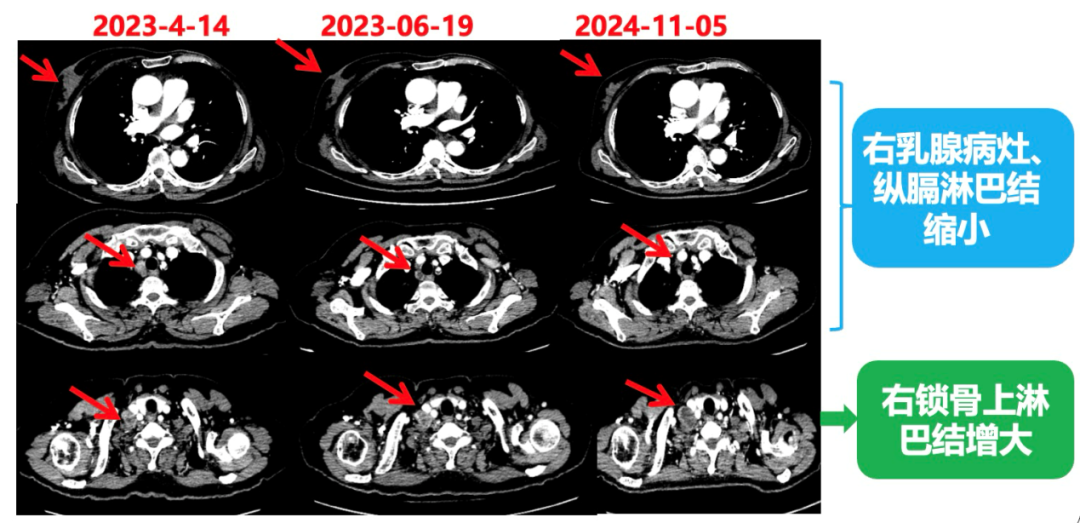

2023.6.26复查PET-CT

1.右乳外上象限乳腺癌病灶(22*16mm),对比2023-04-14 CT(26*24mm)较前缩小,FDG代谢活跃。右侧腋窝小淋巴结(5mm),较前稍缩小,代谢不活跃。右侧锁骨上区、上纵隔淋巴结转移瘤(24*18mm),现大小同前相仿,代谢活跃(SUV:6.7)。

2.现胃贲门部术后改变,术区未见明显异常活性灶。

3.左乳、左侧胶窝术后改变,未见明显异常活性灶。双肺小结节。考虑炎性结节可能,建议复查;双肺门及纵隔另反应性淋巴结。

2024-11-5复查CT:右乳外上象限占位(11mm×9mm),较前明显缩小;上纵隔及右肺门多发淋巴结转移缩小;右锁骨上区淋巴结较前增大。余部位未见肿瘤转移及复发征象。